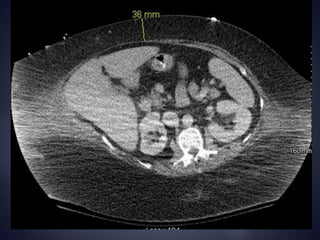

Parastomal hernia

 Abdominal CT scan helpful in c/o difficulty

How are wegoing to get this through that ?

Skin Fascia 9 cm 9cm +2cm = 11cm of Sigmoid Colon 9cm + 6cm = 15cm of Terminal ileum BMI 48.7